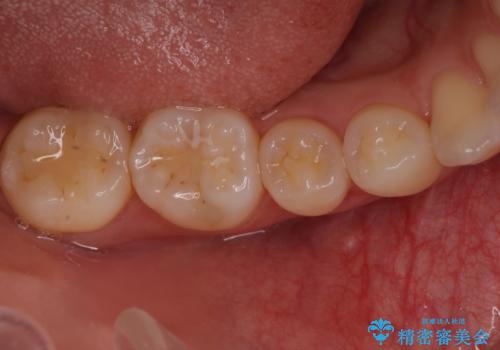

骨の再生治療手術をして10か月経過観察をしたのち、骨を平坦化する手術を行い、治療終了となりました。

・ほとんどの場合、2回目の手術(骨を平坦化する等)が必要になります。